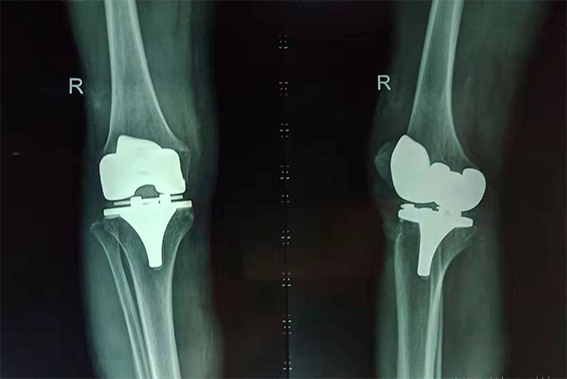

吳奶奶術(shù)后右膝X光片

“頭天做了手術(shù),第三天就能下地走路了,真是太神奇了!這給子女們減輕了不少負擔。”吳奶奶高興地說。目前她正在醫(yī)生的指導下,進行康復訓練。